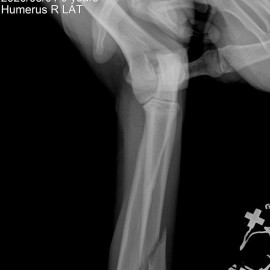

Наш пациент после автотравмы. После осмотра и проведения рентгенологических исследований выл поставлен диагноз - косой диафизарный перелом правой лучевой и локтевой кости со смещением. Была проведена операция - остеосинтез костей правого предплечья.

Снимки до операции.